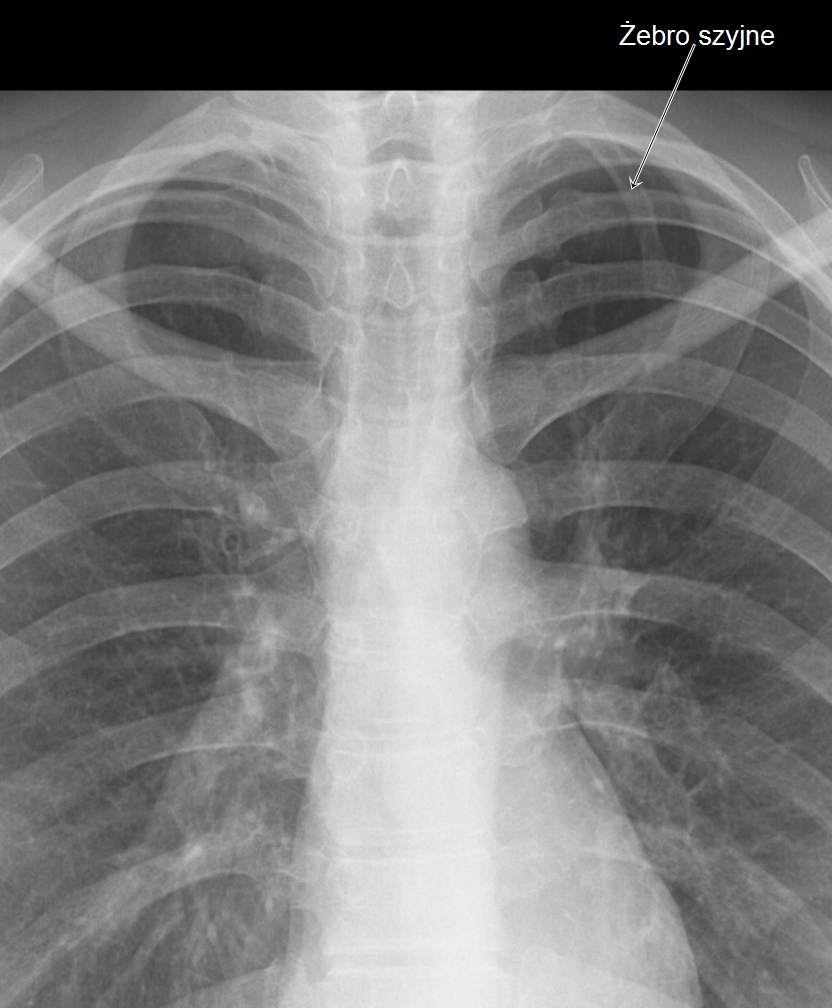

Wizyta u lekarza oraz prześwietlenie RTG potwierdziły, że żebra nie są ani złamane, ani pęknięte, a mocny ból spowodowany jest poważnym stłuczeniem lewej strony klatki piersiowej. Póki co aktywność na poziomie zero i kolejna wizyta kontrolna w przyszłym tygodniu.